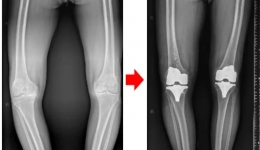

• 守护膝关节健康,且行且珍“膝”——严重膝关节病变,膝关节置换能帮到您!

守护膝关节健康,且行且珍“膝”——严重膝关节病变,膝关节置换能帮到您!